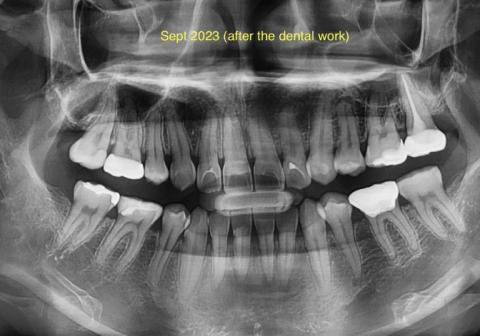

This panoramic dental X-ray (taken after dental work in September 2023) shows multiple restored teeth, including fillings and treated posterior teeth. The roots and surrounding bone are visible across the upper and lower jaws, allowing evaluation of healing, hidden infection, and overall oral health.

Some areas show treated teeth with restorations, while other regions require close monitoring for possible residual or recurrent infection.

Based on the X-ray appearance, the most likely findings include:

Teeth with previous dental restorations

Areas consistent with past infection that appear treated

Bone levels that require monitoring around treated roots

Risk of residual infection if healing is incomplete

A clinical exam and comparison with earlier X-rays are required to confirm full healing.